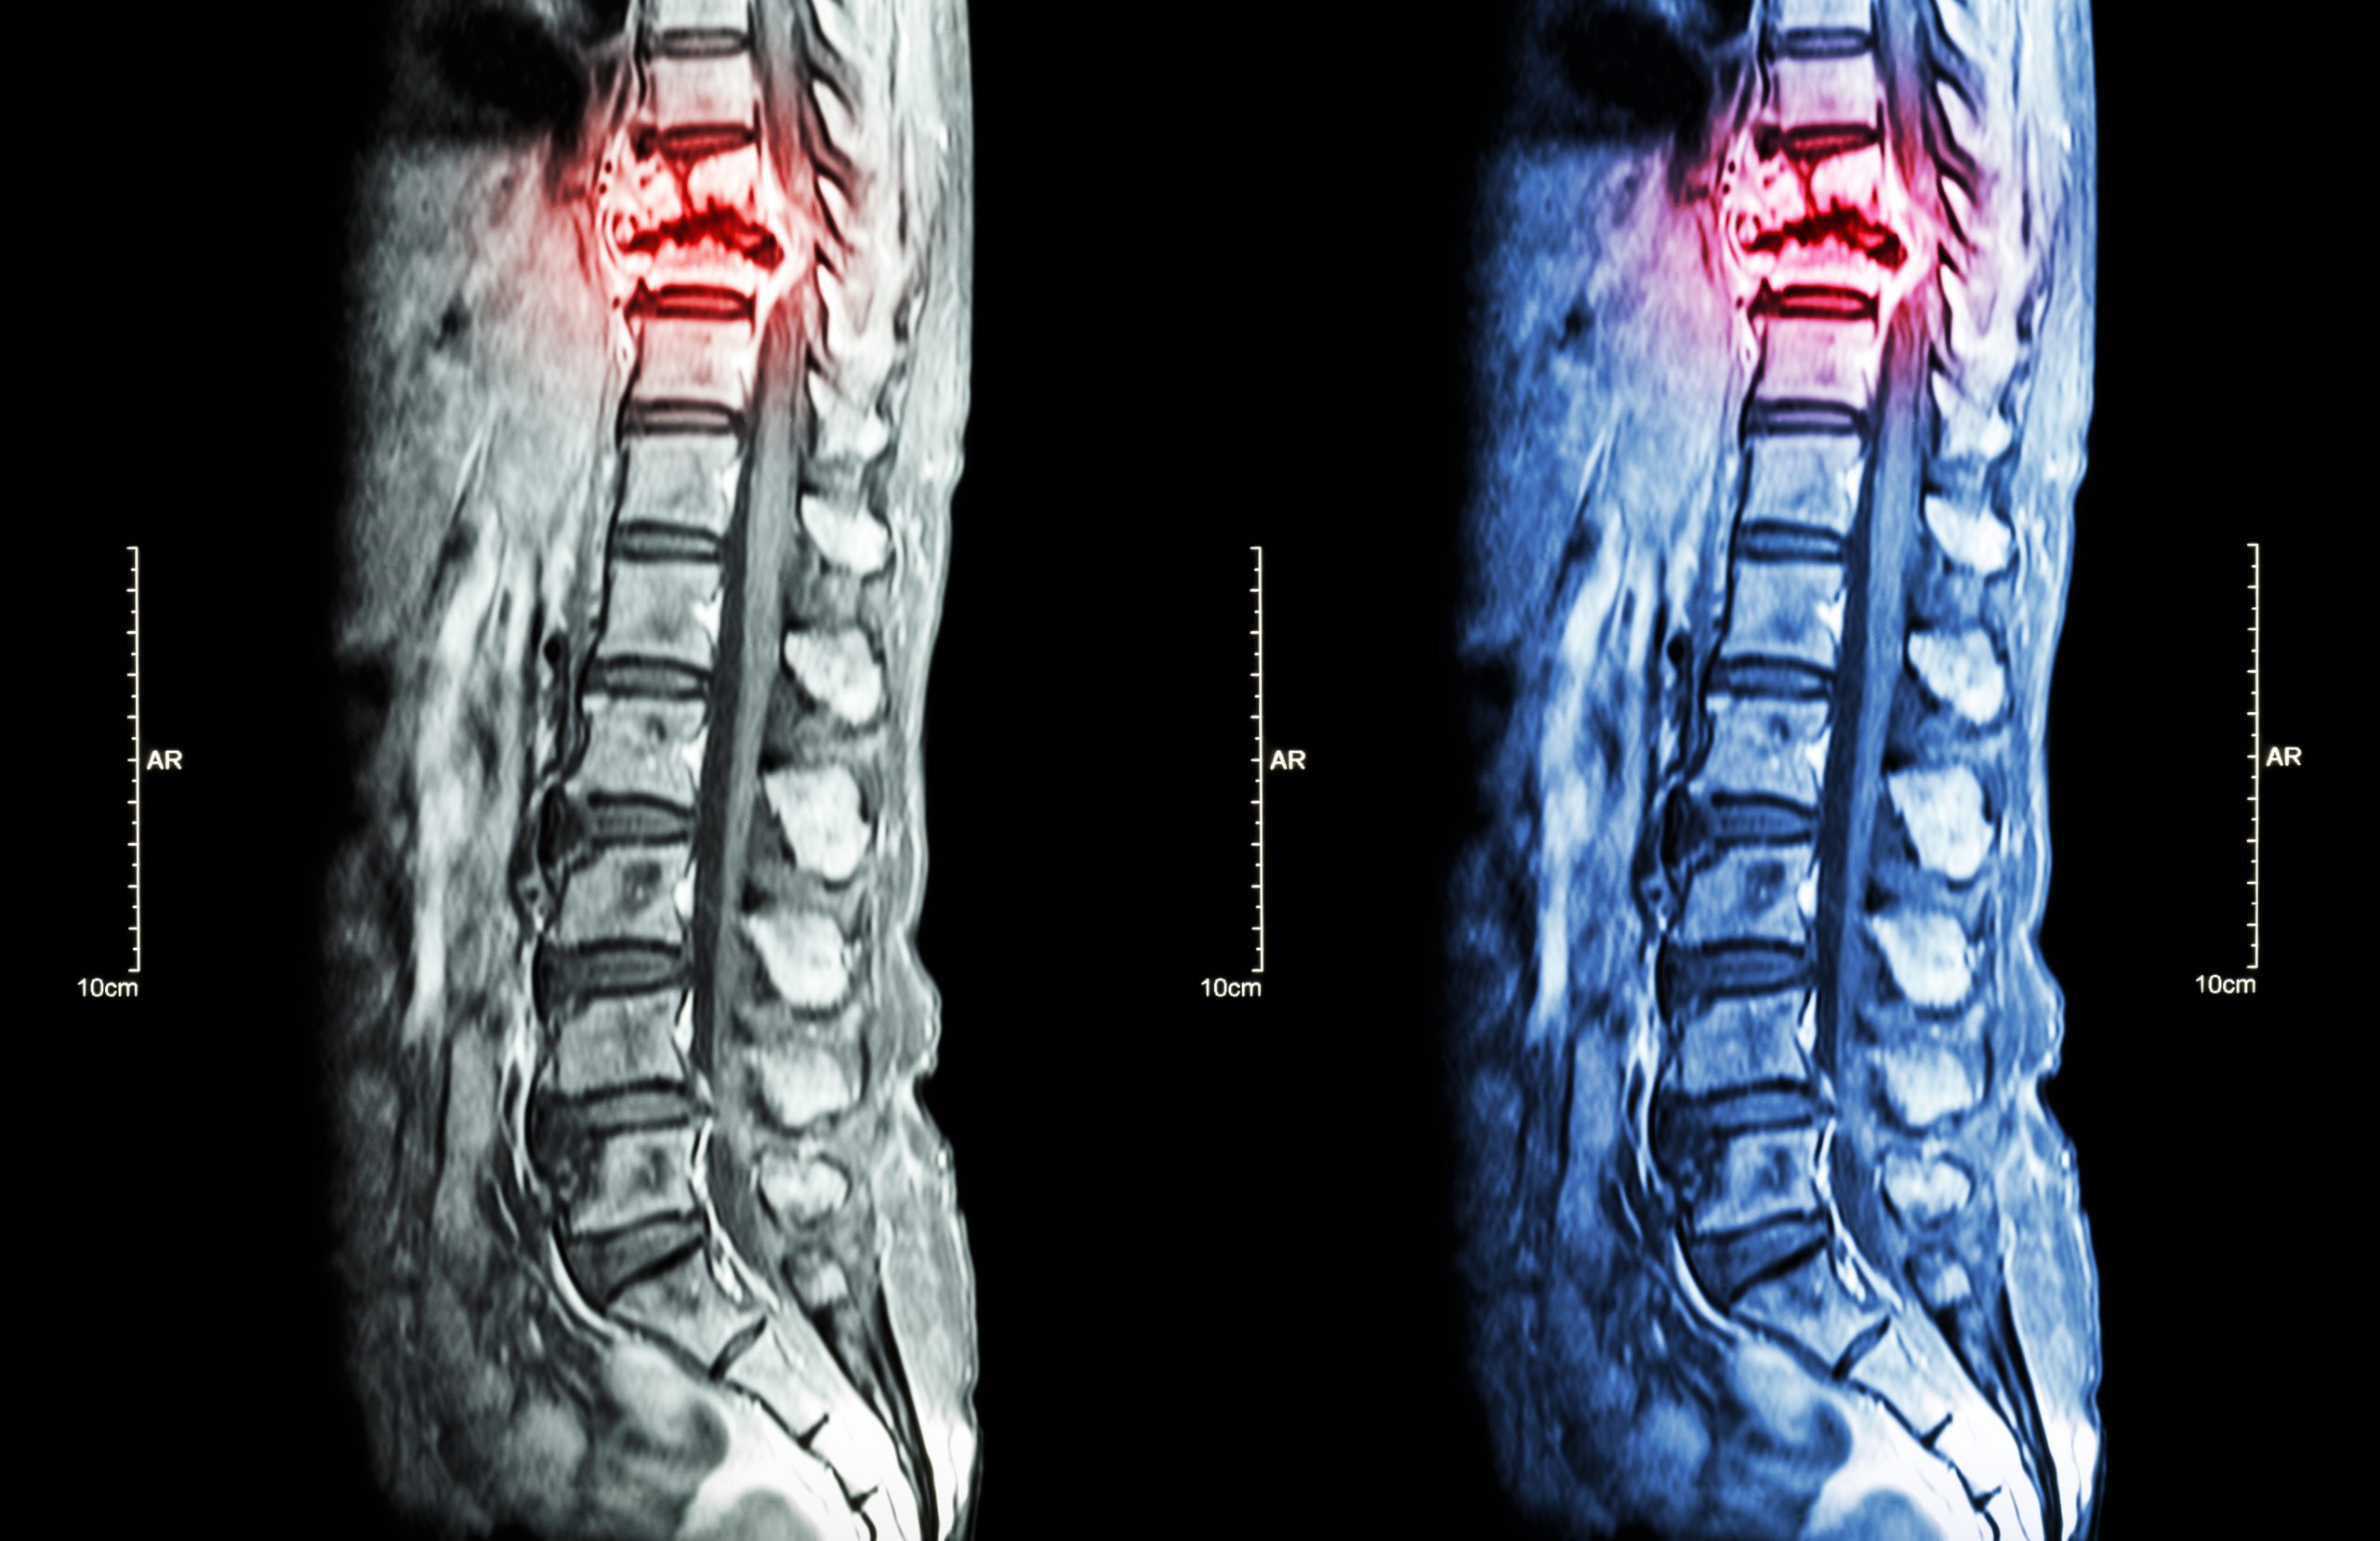

SPINAL CORD INJURY REHABILITATION

At Neurability Therapy, we provide specialized therapy services for individuals recovering from spinal cord injuries (SCI). Our goal is to help every client maximize function, adapt to new challenges, and reclaim their quality of life through expert, evidence-based care.

Spinal cord injury is categorized by level (where the injury occurs on the spine) and severity (complete or incomplete). The higher the injury, the more widespread the impact.